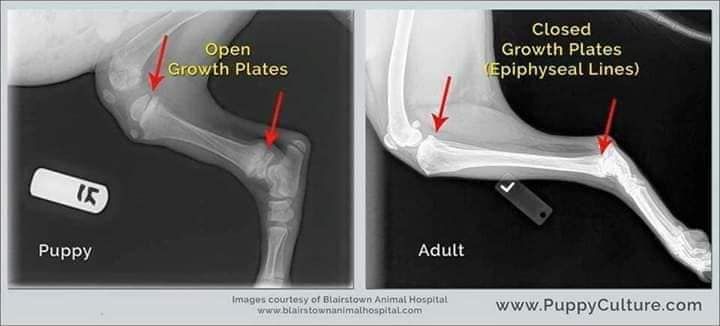

Lorsque vous obtenez vos chiots âgés de 8/12 semaines, veuillez garder cette image à l'esprit!!

Leurs os ne se touchent même pas encore. Ils marchent si gentiment avec de grosses pattes souples et un mouvement bancal parce que leurs articulations sont entièrement constituées de muscles, de tendons, de ligaments recouverts de peau. Rien ne s'emboîte étroitement ou n'a encore de véritable prise.

Lorsque vous les faites courir de manière excessive ou ne restreignez pas leur exercice pour les empêcher d'en faire trop pendant cette période, vous ne leur donnez pas la chance de grandir correctement. Chaque grand saut ou course de rebond excitée provoque des impacts entre les os. En quantités raisonnables, ce n'est pas problématique et c'est l'usure normale dans laquelle chaque animal s'engage.

Mais lorsque vous laissez le chiot sauter de haut en bas du salon ou du lit, l'emmener pour de longues promenades / randonnées, vous endommagez cette articulation en formation.